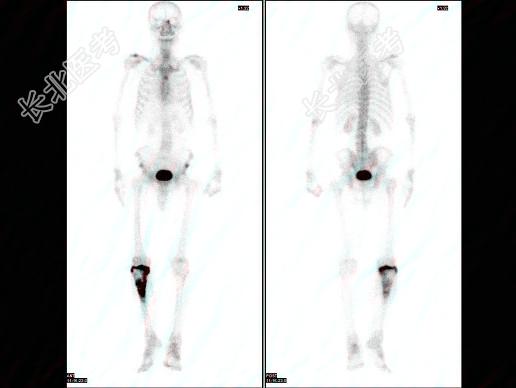

多项选择题男,71岁, 右胫骨骨巨细胞瘤术后4年,无明显不适, 行全身骨显像如图,可能的诊断是 ( )

A、右胫骨术后改变

B、右胫骨肿瘤复发

C、右胫骨骨肉瘤

D、未见骨转移改变征象

E、骨盆有骨转移瘤